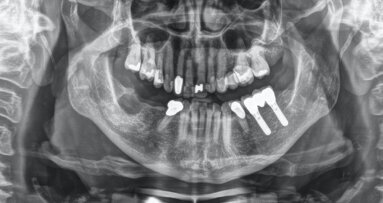

Este caso clínico ilustra el Concepto de Prevención Personalizada, que se ha desarrollado para evitar que los factores de riesgo de la salud general ...